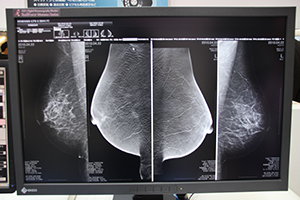

トモシンセシス表示にも対応したPlissimo MG

マンモグラフィ専用画像診断ワークステーションのPlissimo MGでは,これまでのワークステーションタイプに加え,医療現場からのニーズに応え,拡張性に優れたサーバ・クライアントタイプのPlissimo MGが初出展された。スタンドアロンではなくネットワーク対応とすることで複数の端末で読影できるなど,施設の運用に応じたシステムが構築できる。

また,Plissimo MGに搭載できる最新アプリケーションとして,全自動三次元乳腺密度評価ソフトvolpara(参考出品)のデモンストレーションも行われた。volparaは,マンモグラフィの診断能を低下させる原因のひとつであり,日本人に多く見られるデンスブレストに対する新たなソリューション。乳房の体積と乳腺の体積,乳腺密度を解析し数値化,三次元表示することで,読影者により判断が異なっていたデンスブレストに客観性と再現性を持たせることに成功した。このソフトを用いることでデンスブレストの被検者が精査を納得して受けられるきっかけになると期待される。

読影を効率化するPlissimo MGの専用インターフェイス |

デンスブレストの診断を支援するvolpara |